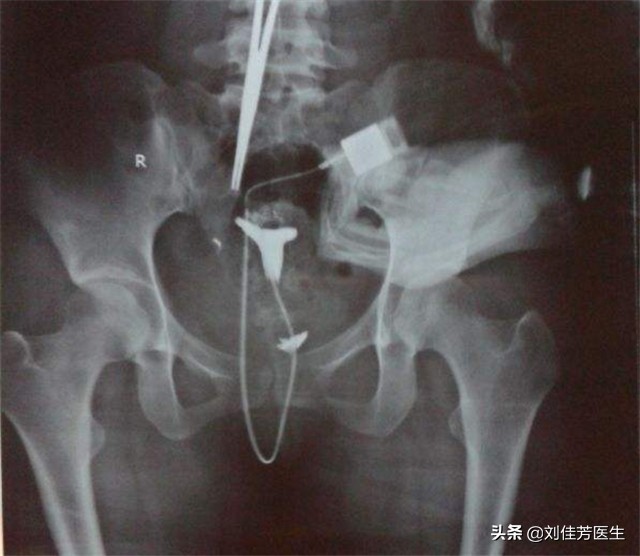

平常生活中,患有这种炎症不通引起的输卵管堵塞的话,会有小腹两侧针扎般的刺痛感。从输卵管造影上,可以看出来,造影是很不均匀的。炎症不通的输卵管堵塞,是最容易出现宫外孕的类型。在中医的治疗方案中,经前要注重活血化瘀,清宫也要重视,同时使用二号热敷药。而在月经经后,治疗措施会有所改变,以消炎为主,凉血为辅。